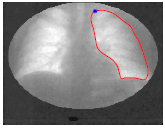

Sketch Initialized Snakes for Rapid, Accurate, and Repeatable Interactive Medical Image Segmentation,

T. McInerney and M.R. Akhavan Sharif,2006 IEEE International Symposium on Biomedical Imaging, Arlington, Virginia, April 2006, pages 398-401.

| SketchSnakes: Sketch-Line Initialized Snakes for Efficient Interactive Medical Image Segmentation, T. McInerney, Computerized Medical Imaging and Graphics, 32, 2008, pages 331-352. |